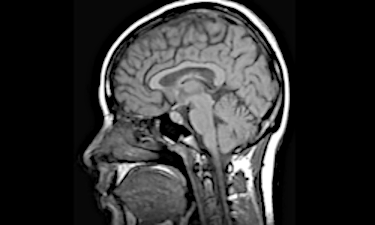

We employ multiple neuroimaging techniques—including structural MRI, diffusion tensor imaging (DTI), functional connectivity, and functional MRI—to investigate how the brain is altered in mental disorders. These complementary approaches allow us to explore both brain structure and function, providing a more complete picture of the neural systems that may be disrupted. By integrating different types of data, we can detect subtle changes in connectivity and circuitry that might otherwise remain hidden.